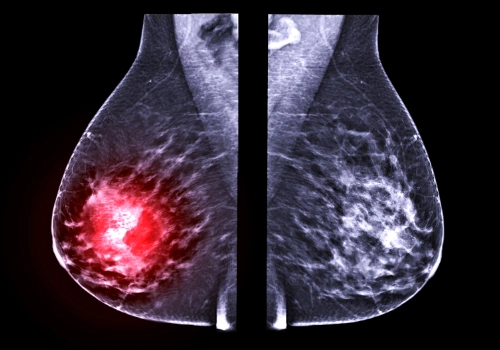

How Recurrent Breast Cancer Is Diagnosed

If recurrence is suspected, your care team may recommend imaging tests such as mammography, ultrasound, MRI, PET scan, or CT scan, along with a biopsy to confirm the diagnosis. Testing may also determine hormone receptor and HER2 status, which play a key role in treatment planning.